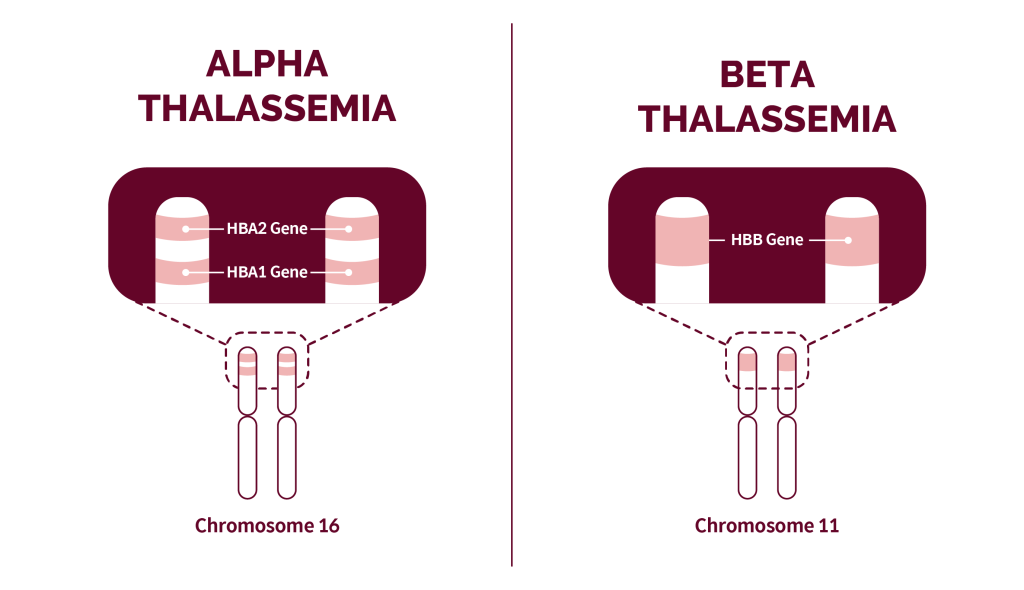

Thai nhi bị thiếu máu di truyền: các nhóm gen cần biết theo cách tổng quát

Bạn không cần nhớ hết tên gen. Bạn cần nhớ các nhóm bệnh. Mỗi nhóm kéo theo một hướng xét nghiệm.

Nhóm một: bệnh huyết sắc tố

Đây là nhóm thường gặp nhất trong thực hành. Điển hình là thalassemia. Cơ chế là giảm tổng hợp chuỗi globin. Thai có thể thiếu máu từ nhẹ đến rất nặng do nhóm này thường được định hướng từ tầm soát bố mẹ.

Nhóm hai: bệnh màng hồng cầu

Hồng cầu dễ vỡ do bất thường cấu trúc màng. Trẻ có thể thiếu máu tan máu. Mức độ thay đổi. Có gia đình có tiền sử vàng da kéo dài hoặc lách to. Thai nhi bị thiếu máu di truyền do nhóm này ít gặp hơn, nhưng cần nghĩ khi tiền sử gia đình rõ.

Nhóm ba: bệnh men hồng cầu

Hồng cầu thiếu một số men chuyển hóa nên dễ bị tan trong một số bối cảnh. Có trường hợp biểu hiện rõ sau sinh. Có trường hợp nặng hơn và cần truyền máu. Thai nhi bị thiếu máu di truyền ở nhóm này thường không được chẩn đoán chỉ bằng một xét nghiệm đơn lẻ. Cần panel phù hợp theo tư vấn huyết học.

Nhóm bốn: rối loạn tạo hồng cầu bẩm sinh

Tủy tạo hồng cầu không hiệu quả. Thiếu máu có thể dai dẳng. Một số thể cần truyền máu sớm. Nhóm này thường được nghĩ tới khi các nhóm trên không giải thích được. Thai nhi bị thiếu máu di truyền do nhóm này hay cần xét nghiệm di truyền chuyên sâu hơn.